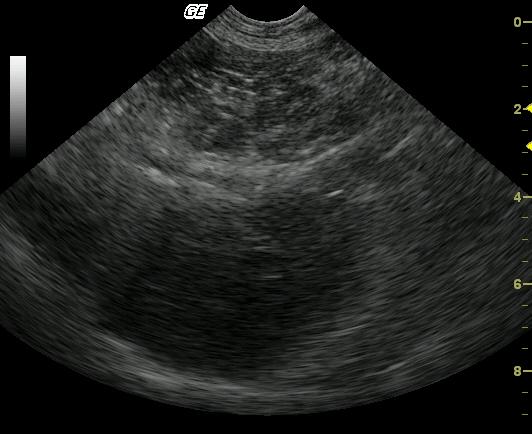

Moderate pancreatitis with peripancreatic inflammation in a 3 Year Old MN Labrador Retriever

Moderate pancreatitis with peripancreatic inflammation.

Severe, uniform pancreatic enlargement with a diffusely, moderately hypoechoic parenchyma is present. The bordering fat is mildly to moderately echogenic.